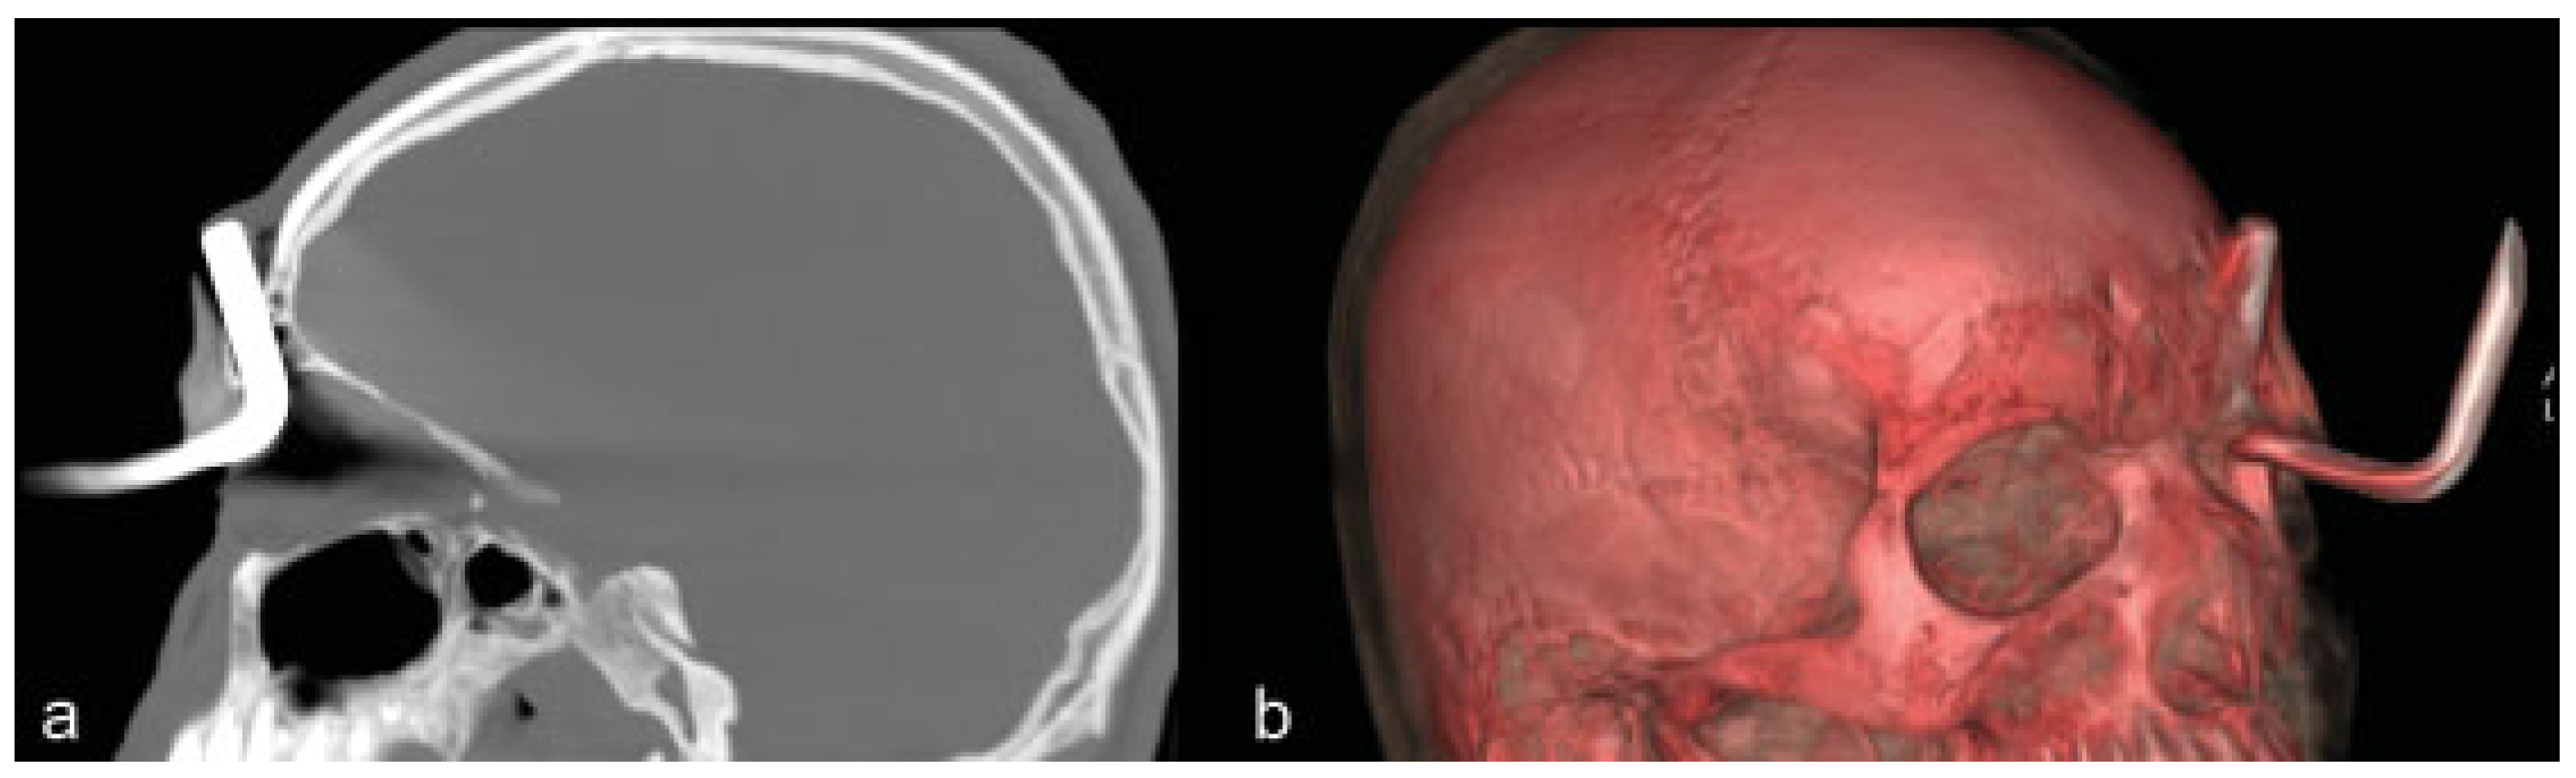

Transorbital Orbitocranial Penetrating Injury with an Iron Rod

:Case Report